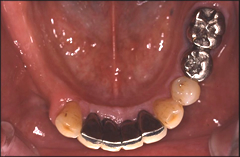

インプラントの形や特徴をよく理解した上で、担当医の指導に従って、ブラッシングを行い、歯垢や歯石の沈着を防ぎます。歯を長持ちさせるために、定期的な担当医の検診を受けることをおすすめします。